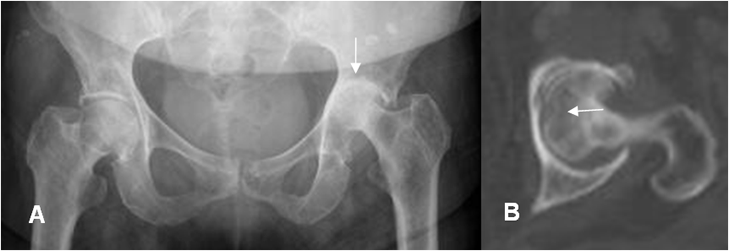

Fig 142 B. Artritis séptica.

A: Rx AP. Pérdida del espacio articular en la cadera izquierda, sin presencia de osteofitos.

B: TAC axial. Adicionalmente se encuentra alteración en la densidad de la cabeza femoral, por osteomielitis asociada.